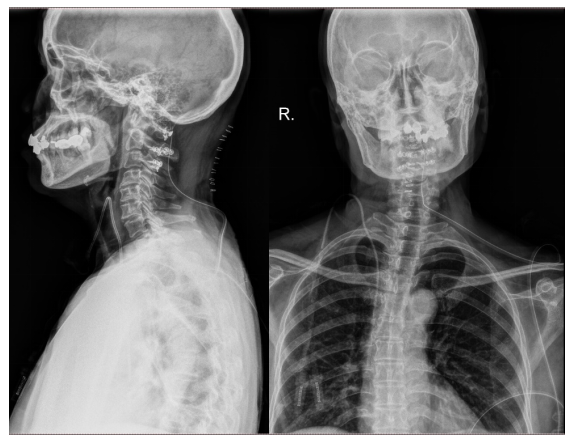

病例2 女性 61岁

以“四肢麻木无力6个月”为主诉入院,自诉上肢麻木持物不稳,下肢麻木行走费力。专科查体:四肢肌力Ⅳ级,双上肢Hoffmann征阳性,双下肢Babinski征阳性。双侧膝腱反射活跃。

结合术前影像学资料,病变位于髓外硬膜下,位于颈髓腹侧,边界尚清,T1等信号,T2略高信号,影像学上似起源于腹侧硬膜,考虑脊膜瘤可能。

行“颈1-3椎管内肿瘤切除+椎板回植术”,术后患者四肢肌力明显改善,病理征消失。